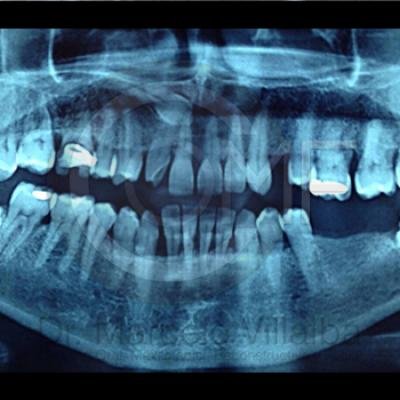

Generalmente en el momento de su erupción presentan procesos inflamatorios en la zona posterior de la cavidad oral, infección, dolor, movilidad de órganos dentarios, mal sabor en boca, mal olor en boca (halitosis), infección, incluso edema (aumento de volumen en tejido blando de la cara y/o boca) y complicaciones si no son atendidos. En el apoyo de diagnóstico se pueden requerir radiografías panorámicas y hasta tomografía en caso de ser necesarios.